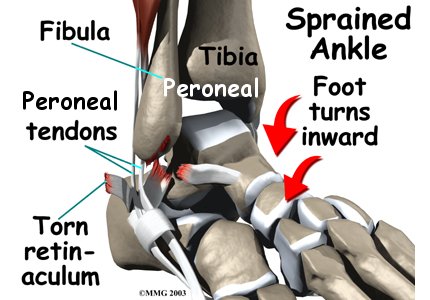

The primary muscles supporting the are the peroneals. These two muscles and their tendons lie along the outside of the lower leg bone (fibula) and cross behind the lateral malleolus (the outside ankle bone).

The tendons of the peroneal muscles pass together through a groove behind the lateral malleolus. The tendons are kept within the groove by a sheath that forms a tunnel around the tendons. The surface of this sheath is reinforced by a band of ligament called a retinaculum. Contracting the peroneals makes the tendons glide in the groove like a pulley. This pulley action points the foot downward (plantarflexion) and outward (eversion).

The main cause of peroneal tendon subluxation is an ankle sprain. A sprain that injures the ligaments on the outer edge of the ankle can also damage the peroneal tendons. During the typical inversion ankle sprain, the foot rolls in. The forceful stretch on the peroneals can rip the retinaculum that keeps the peroneal tendons positioned in the groove. As a result, the tendons can jump out of the groove. The tendons usually relocate by snapping back into place.

The injury to the retinaculum may be overlooked at first while treatment focuses on the injury to other ankle ligaments. This means the subluxation may begin much later, and it may not seem to be caused by the initial ankle sprain. If not corrected, this snapping of the tendons can become a chronic and recurring problem.

An acute dislocation of the peroneal tendons is rare. It occasionally happens during sport activities that force the foot up and in, for example during skiing, ice skating, or soccer. At the moment the foot turns up and in, the peroneals violently contract to protect the ankle. This can cause the retinaculum to tear, allowing the tendons to slip out of the groove.